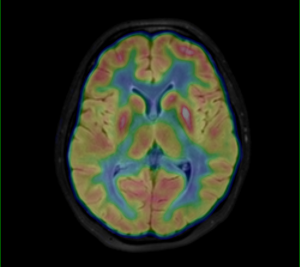

PET vyšetrenie mozgu s 18F-FDG

Diagnostika neurodegeneratívnych ochorení, lokalizácia epileptogénnej zóny u farmakorezistentnej epilepsie